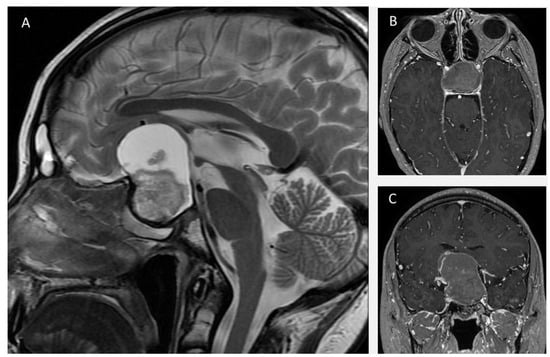

3.2.1. Case 1